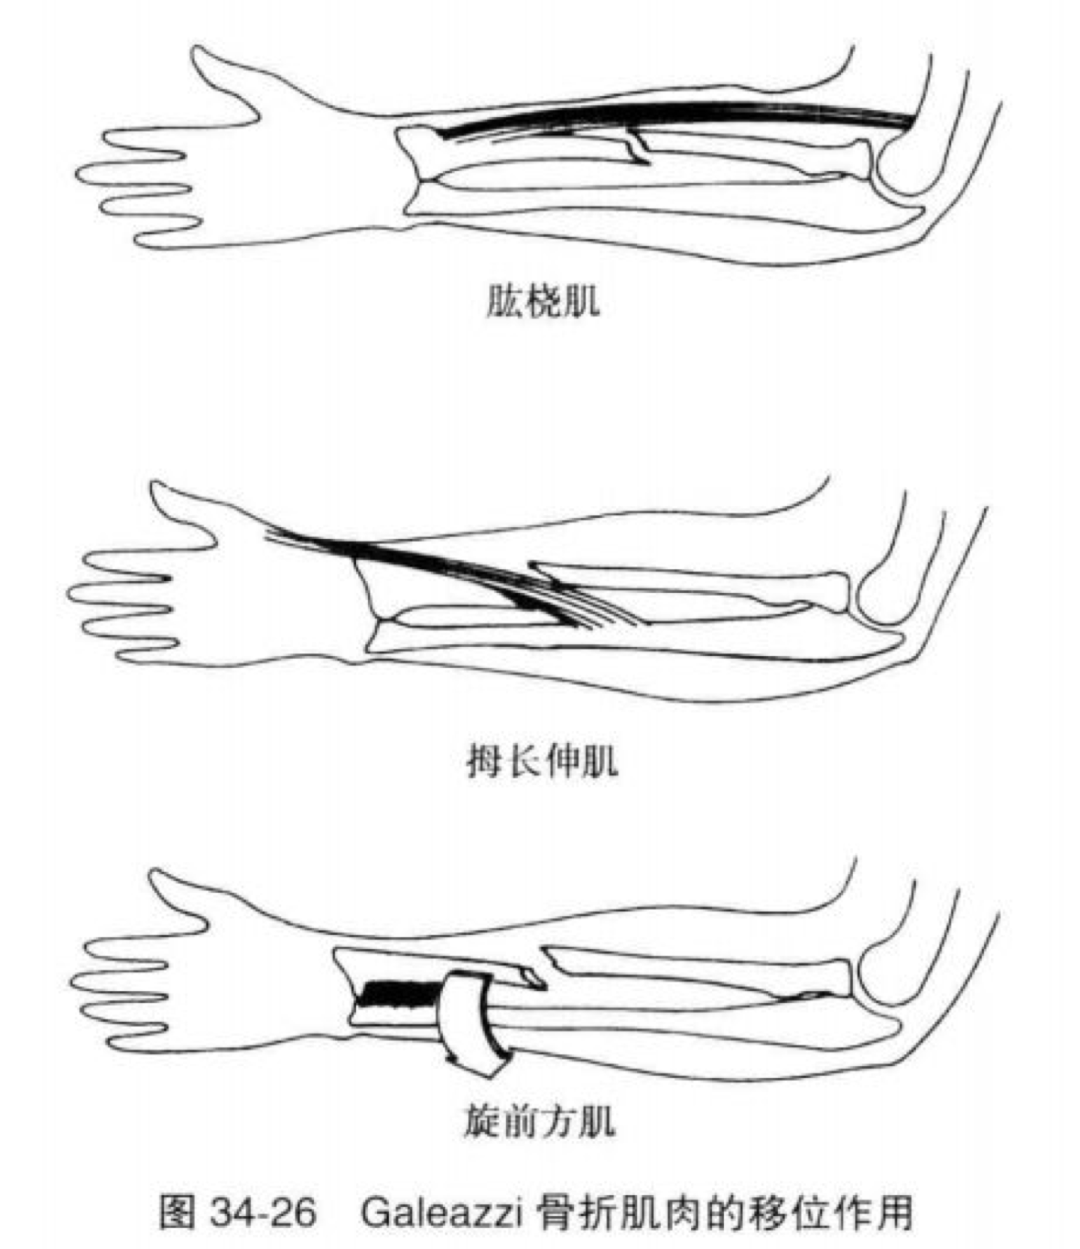

Campell 在1941年指出,Galeazzi 骨折是一种必须手术治疗的骨折。通常认为非手术治疗由于固定不是特别牢固,存在固定失败的潜在风险。由于肌肉的牵拉很容易导致骨折再移位,从而影响下尺桡关节的稳定。包括:1、旋前方肌的收缩,使桡骨远折段向尺骨靠拢,并牵拉其向近侧及掌侧移位;3、外展拇肌及伸拇肌使桡骨远折段向尺骨靠拢,向近侧移位短缩。